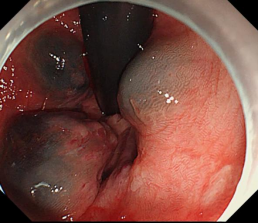

食管胃底静脉曲张内镜下套扎、组织胶治疗

肝硬化食管和胃底静脉曲张破裂出血的内镜下组织胶注射和套扎序惯治疗